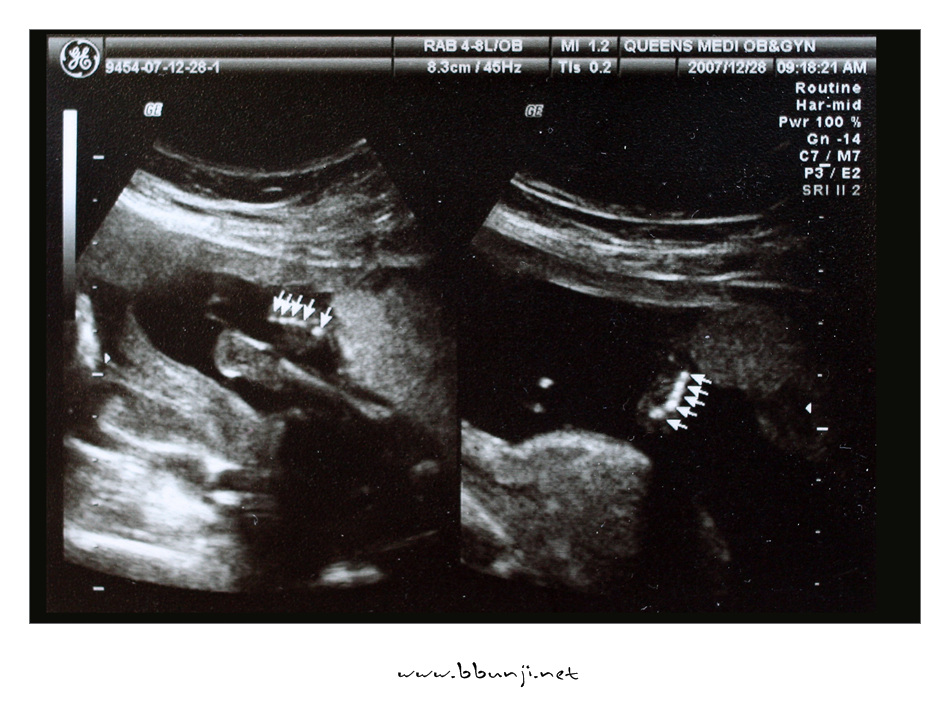

발가락 손가락 갯수도 확인하고 별다른 이상이 없는지 보고 왔습니다.

성별 알아서 출산용품 미리 준비할려고 했더니 병원에서 아직 안가르쳐 주네요.